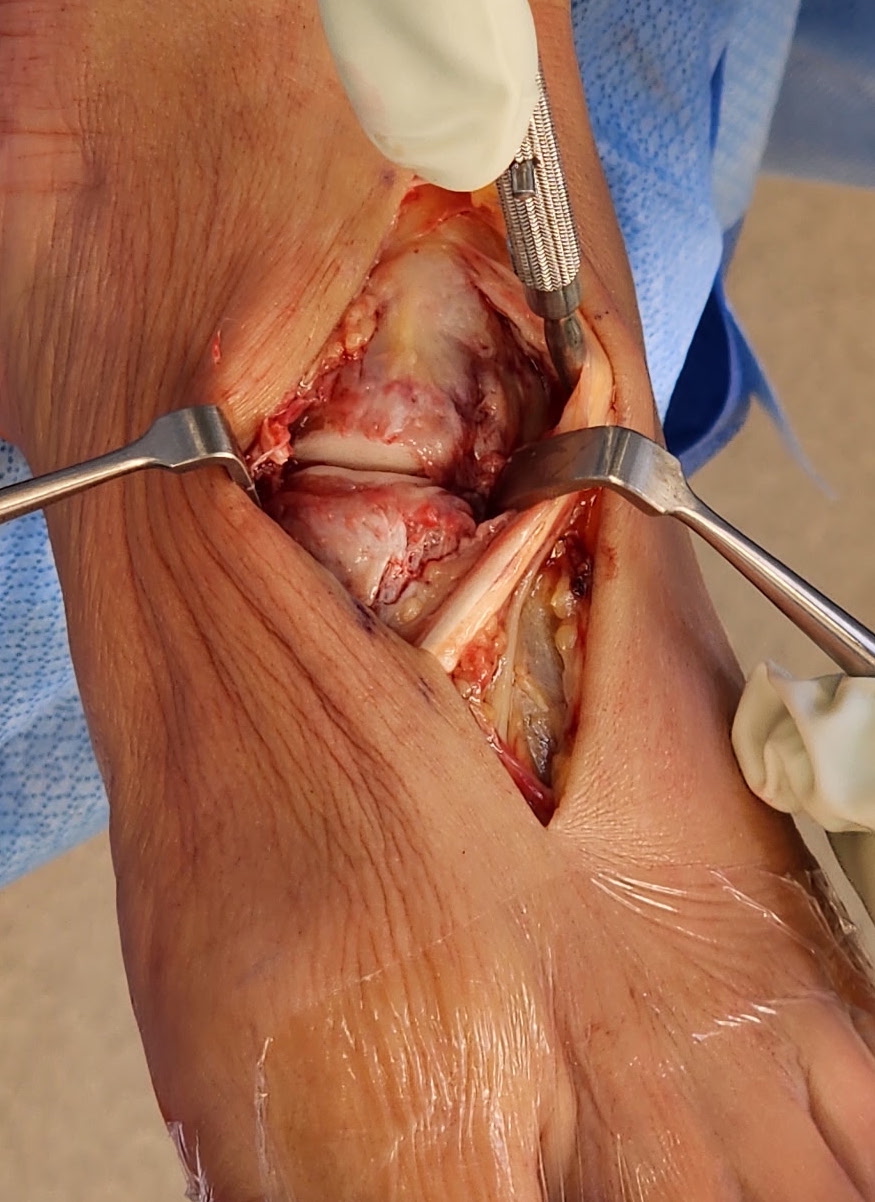

Approach and reduction

Dorsal incision between 1st and 2nd metatarsal

- protect branches of superficial peroneal nerve

- release EHL tendon and retract laterally for 1st TMT / medially for 2nd TMT

- retract EDB more proximally either way to approach 1st TMT / 2nd TMT

- pass artery clip under dorsalis pedis / deep peroneal nerve and mobilize

Reduction

- medial incision over medial cuneiform

- clamp medial cuneiform to base 2nd metatarsal